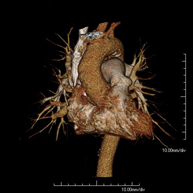

Prova diagnòstica no invasiva que consisteix en l'estudi de l'artèria aorta abdominal a través de l'obtenció d'imatges d'alta definició anatòmica mitjançant l'ús d'un equip de TC (Tomografia Computeritzada) i de contrast iodat. La qualitat de les imatges permet realitzar reconstruccions en 2D i 3D gràcies a estacions de treball especialitzades en l'estudi arterial. Està indicat en aquells pacients amb malaltia vascular (arteriosclerosi), en aneurismes d'aorta, en pacients amb dolor abdominal de possible origen vascular, en estudis prequirúrgics de lesions adjacents a l'aorta abdominal com a "mapa" vascular. La informació obtinguda de manera no invasiva és indispensable per als pacients que requereixen tractament percutani o quirúrgic. En aquells pacients que només requereixen seguiment de les lesions vasculars, aquesta tècnica és la tècnica no invasiva d'elecció juntament amb l'angio-RM. - Angio-TC Artèries renals

Prova diagnòstica no invasiva que consisteix en l'estudi de les artèries renals a través de l'obtenció d'imatges d'alta definició anatòmica mitjançant l'ús d'un equip de TC (Tomografia Computeritzada) i de contrast iodat. La qualitat de les imatges permet realitzar reconstruccions en 2D i 3D gràcies a estacions de treball especialitzades en l'estudi arterial. Està indicat en aquells pacients amb malaltia vascular (arteriosclerosi), en aneurismes d'aorta, en pacients amb dolor abdominal de possible origen vascular, en estudis prequirúrgics de lesions adjacents a l'aorta abdominal com a "mapa" vascular. La informació obtinguda de manera no invasiva és indispensable per als pacients que requereixen tractament percutani o quirúrgic. En aquells pacients que només requereixen seguiment de les lesions vasculars, aquesta tècnica és la tècnica no invasiva d'elecció juntament amb l'angio-RM. - Angio-TC Aorto-ilíac

Prova diagnòstica no invasiva que consisteix en l'estudi de les artèries ilíaques i l'aorta abdominal a través de l'obtenció d'imatges d'alta definició anatòmica mitjançant l'ús d'un equip de TC (Tomografia Computeritzada) i de contrast iodat. La qualitat de les imatges permet realitzar reconstruccions en 2D i 3D gràcies a estacions de treball especialitzades en l'estudi arterial. Aquesta prova està especialment indicada com estudi prequirúrgic (mapa vascular) abans d'intervencions percutànies o quirúrgiques d'aorta abdominal, com l'estudi complementari en pacients amb isquèmia de membres inferiors, etc. - Colonoscòpia virtual

A non-invasive diagnostic test that involves studying the abdominal aorta by obtaining high-definition anatomical images using CT (computed tomography) equipment and iodinated contrast. With the aid of workstations specialised for arterial studies, the image quality supports 2D and 3D reconstructions. It is indicated in patients with vascular disease (atherosclerosis), aortic aneurysms, abdominal pain of possible vascular origin, pre-surgical studies of lesions adjacent to the abdominal aorta as a vascular ‘map’, etc. Information obtained non-invasively is indispensable for patients requiring percutaneous or surgical processing. In patients who only require tracking of vascular lesions, this technique is the non-invasive technique of choice, together with MRI angiography.